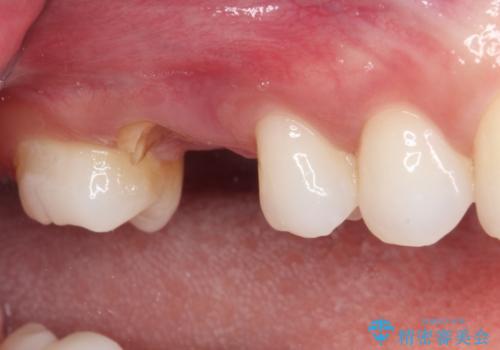

抜歯が必要であることは患者様自身も理解されており、インプラントによる欠損補綴治療を希望されていらっしゃいました。

抜歯前のCTにより、インプラントを埋入するために必要な歯槽骨量が不足することが予想されたため、サイナスソケットリフトにより上顎洞内の粘膜を挙上して、インプラントを埋入することとしました。

その後は、オールセラミッククラウンにて補綴することとしました。